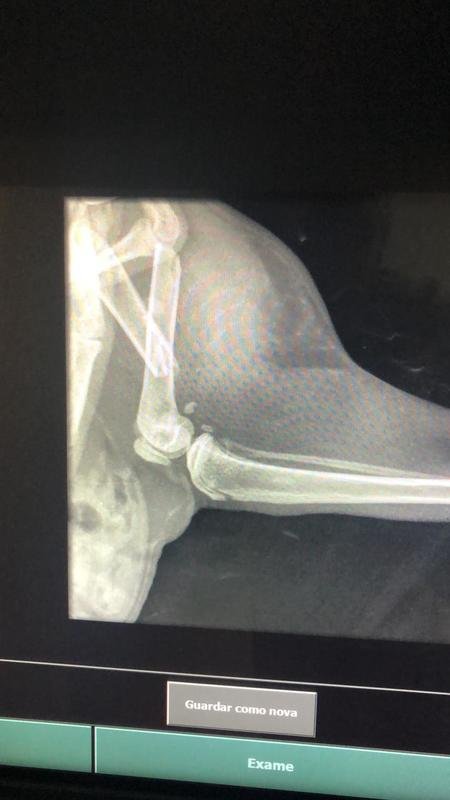

medusa minha gatinha foi atropelada na sexta e largada na rua , e por conta disso está precisando passar por 3 cirurgias, tem duas fraturas no corpo e terá de amputar o rabo. Com todos os gastos, as cirurgias ficaram mais de 3,500 reais, então, precisamos de ajuda para salvarmos ela dessa dor !!